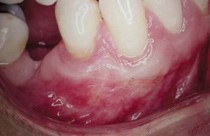

Une greffe gingivale est une chirurgie qui consiste à prélever un greffon (petit morceau de gencive) généralement du palais afin de l’apposer au niveau de la gencive, là où il y a un manque. Le tout est maintenu en place par un pansement parodontal, au besoin.

Nos interventions sont réalisé à l'aide de loupe binoculaire.